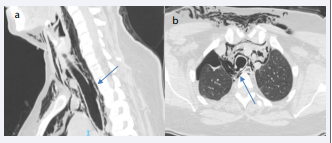

These findings were confirmed by a continuous solution of about 5 mm appreciable in correspondence with the right posterolateral wall of the middle III of the trachea, at the level of D1-D2, extending longitudinally for a length of about 20 mm. Externally to the breach, a thin membrane appeared to delimit a small “pocket” containing air with a maximum axial dimension of 12 mm [Figure 1a, 1b].

a) Tracheal rupture at CT scan. b) CT scan showing tracheal  breach.

Figure 1: a) Tracheal rupture at CT scan. b) CT scan showing tracheal breach.